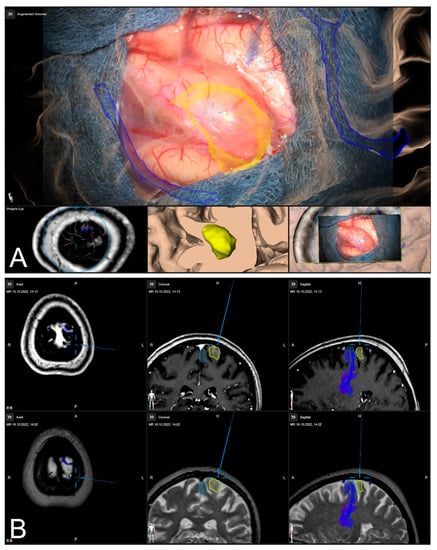

After calibration of the surgical microscope, AR-support including all pre-segmented objects is available. Outlined objects, such as the tumor or vascular or functional risk structures, can then be visualized using the AR display by superimposing the 3D objects in the operating microscope by the integrated HUDs. In parallel, multimodal fused image sets are visualized in the Cranial Navigation Element (Brainlab, Munich, Germany) on a monitor close to the surgical field. In addition, within the Microscope Navigation Element (Brainlab, Munich, Germany) objects can be displayed, e.g., superimposed on the microscope video or within a probe’s eye view of the registered image data. Alternatively, the microscope video can be superimposed on a 3D visualization of the patient data including all objects and relevant pre-segmented structures intuitively relating the microscope video frame and 3D anatomy (see Figure 3).

Figure 3.

After calibration of the microscope, besides HUD-based visualization within the microscope, the Microscope Navigation Element (A) and Cranial Navigation element (B) are displayed on monitors close to the surgical field. The microscope application allows for a visualization of outlined objects (yellow: tumor, blue: precentral gyrus, corticospinal tract) superimposed on the microscope video (A, top), or probe’s eye view, target view or outlined 3D anatomy in relation to the microscope video frame (A, bottom, left to right). In parallel, in the navigation application multimodal fused image sets with outlined structures are visualized in, e.g., axial, coronal, and sagittal view (B).